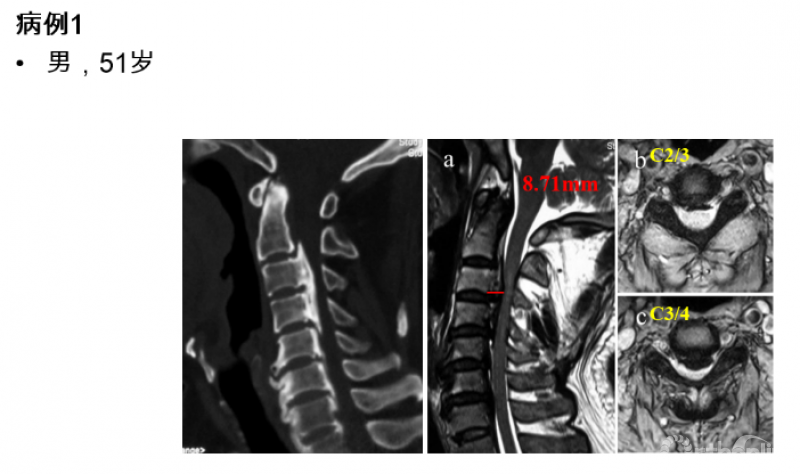

在初步了解颈后路减压手术后脊髓的运动规律及影响因素之后,我们对于如何制定合理的纵向减压范围又做了进一步的研究,初衷是解决临床工作中遇到的一类的临床问题。下面以具有代表性的临床病例进行说明。

图1

从该患者的影像资料可以发现以下特点:致压物主要是来自于脊髓前方的后纵韧带骨化块,造成脊髓腹侧受压。在颈2/3间隙及以上水平,并未造成脊髓明显压迫,但在C3/4间隙水平椎管侵占率陡然增大,是脊髓受压最严重的节段。在这种情况下,颈后路纵向减压范围应该是C3-7、C2-7或者C1-7?

最后,我们回到病例一,利用上述研究结果指导临床决策:C3/4水平致压物中矢径8.71mm>7.1mm,所以C3-7减压势必残留压迫,应选择C2-7减压,术后获得了9.34mm的ACS,充分解除了脊髓压迫(图7)。

图7